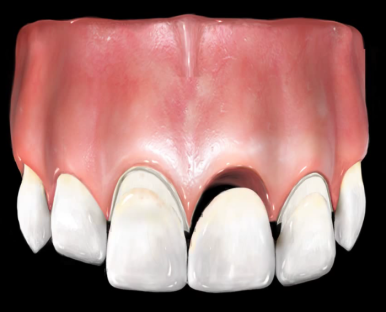

이렇게 전 후 사진비교해보니

브릿지를 하고 훨씬 나아졌습니다.

환자분께서 나머지 다른 앞니들은 충치도 있고 예뻐지려고 라미네이트를 할 예정이라고 하셨기 때문에

조금더 본인 치아색보다 하얀 색으로 진행하였습니다.